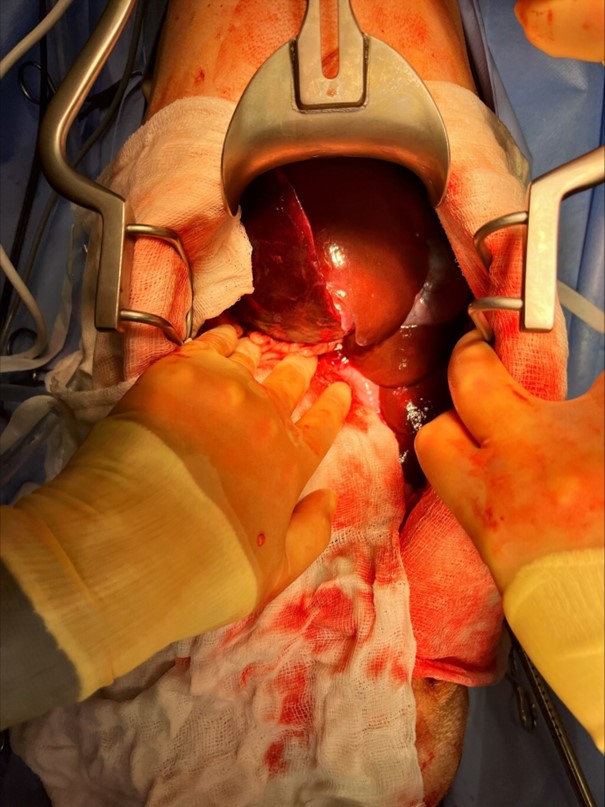

Eastcott Internal Medicine expert Gerard Olivares, a European Specialist in Internal Medicine, took charge of the dramatic multidisciplinary case and successfully operated to remove both torsed liver lobes.

“He was taken straight to theatre for an emergency surgery, where the torsed liver lobes were removed by our surgeons.